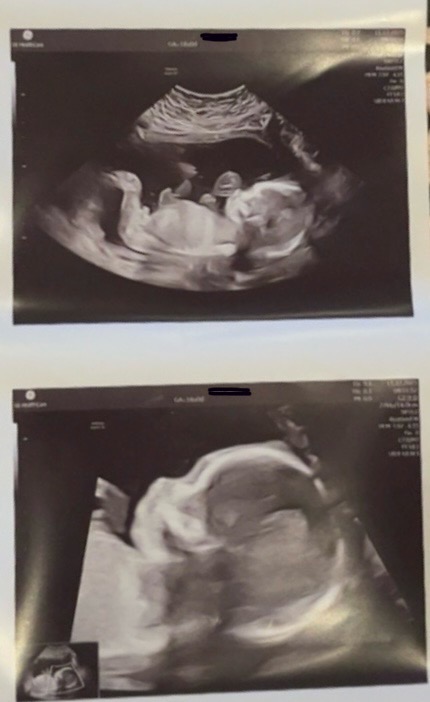

18+0 og ordinær ultralyd!

I dag har vi vært på oul og sett på lillebror! Han koser seg i magen og jeg har begynt å kjenne små spark

Alt vel på ultralyd. Morkake fint plassert.

Den lille nesen!!